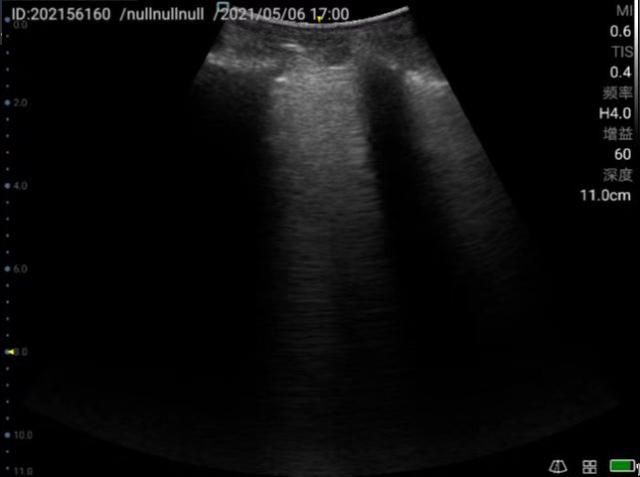

Critical care ultrasonography is a combination of some rapid examination programs, which can perform urgent diagnostic evaluation and can be combined with treatment decisions to effectively improve clinical decision-making.

Ultrasound is now clinically known as “visible stethoscope” as a monitoring and rapid assessment tool for emergency and ICU doctors. Due to the dynamic, real-time and repeatable characteristics of ultrasound, it can not only be used for disease assessment, but also can be dynamically monitored for critically ill patients and provide timely and accurate guidance for treatment.